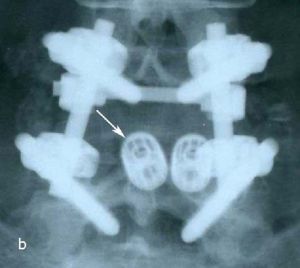

При рентгенографии (Рис.7) и МРТ (Рис.8) поясничного отдела позвоночника выявляется дегенеративный ретролистез L5 позвонка, секвестрированная парамедианная грыжа мп диска L5-S1 слева.

| Рис. 7а,b. Рентгенограмма поясничного отдела позвоночника в боковой (а) и прямой (b) проекциях до операции. Стрелкой показано смещение тела L5 позвонка кзади. | |

Пациенту выполнено оперативное лечение: удаление секвестрированной парамедианной грыжи мп диска L5-S1 слева из минидоступа, миниинвазивная транспедикулярная фиксация L5-S1 титановой конструкцией.

При контрольной рентгенограмме отмечено правильное положение транспедикулярной системы и кейджа на уровне L5-S1 позвонков. (Рис.9)